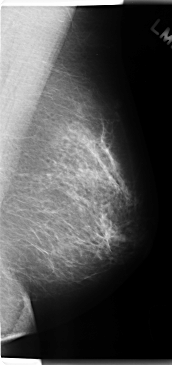

C_0201_1.RIGHT_CC

C_0201_1.LEFT_CC

LEFT_CC LINES 4792 PIXELS_PER_LINE 2424 BITS_PER_PIXEL 12 RESOLUTION 50 NON_OVERLAY